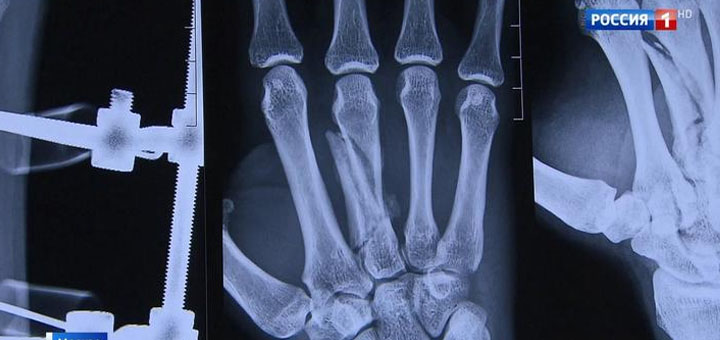

Еще недавно врач и пациент даже поздороваться за руку не могли. Страшная авария едва не сделала тренера по боям без правил инвалидом – кисти от запястий до кончиков пальцев были раздроблены. Сложнейшая операция — и вот результат.

«Эта рука — к ней сразу вернулась чувствительность. Я ждал, что она будет болеть, но она не болела. Удивительно, учитывая, что туда засунули железку, которая до конца жизни будет стоять в руке», — говорит Александр Колесников.

Нить, которой хирурги сшивают поврежденные нервы и сосуды, тоньше человеческого волоса, и чтобы все хорошо видеть, врачи использовали специальные очки. Увеличение всего в 2,5 раза — это абсолютно не соответствовало никаким современным стандартам. На смену очкам пришел новейший медицинский микроскоп с самыми передовыми технологиями. Благодаря этому спортсмену Александру Колесникову спасли руки.